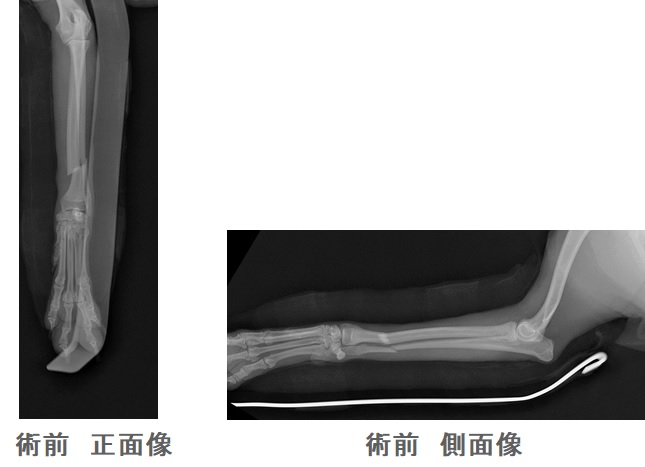

ポメラニアンのココちゃんは遊んでいてイスから落下し、左の前腕(橈骨・尺骨)を骨折しました。

トイ犬種の橈骨尺骨骨折は高いところから落ちたりすることで、良く起こる骨折です。

手術は橈骨の正面と外側面に薄いプレートを当てて、整復・固定します。

強すぎる固定は骨が痩せていくことが多いので、少し弱めの固定を行い、30日ほどで正面のプレートをはずします。